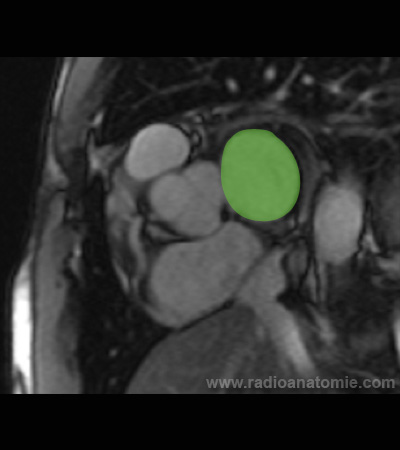

Radioanatomie et plans de coupe en IRM cardiaque

Oreillette gauche